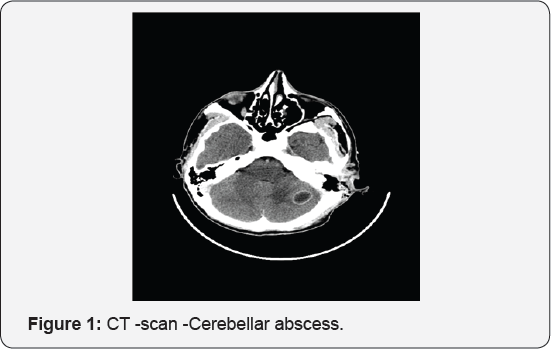

X-ray: mastoid Schuller, view show only erosion of the mastoid bone. CT scan, with i.v. contrast, confirm the diagnosis not only the destruction of the mastoid cells ,with osteitis of the walls, internal mastoid cortical, or of the tegmen tympany or antri ,erosion of the bony walls of the lateral sinus, horizontal semicircular channel, also presence of endocranial lesions in this case meningoencephalitis, extradural abscess and posterior cranial fossa -cerebelar abscess .Repeted at every 7 days permit evaluation in time of the process, abscess formation ,capsule formation and optimum moment for drainage (Figure 1 & 2). MRI offer a better exposure of soft tissues and inflammation saw is ideal for the brain showing difference between cerebritis and edema, also thrombosis of the venous sinuses [1-6].

After 2 weeks CT -scan revealed a large cerebellarabscess mature with clear capsule and was drained using a retro sigmoidcraniotomy. The child had an uneventful recovery. The pus from the mastoid process and cerebellar abscess revealed the same Staphilococcusaureus sensible to AB in use so we continue the same regimen for 6 weeks. He left the hospital in a good shape, with dry ears, a slight dizziness, walking on his feet [8]. He was called for follow up every month, to clean the cavity and for adenoidectomy but a never saw him. 10 years later I have the surprise to see him in emergency, now a 23 years young man, with the other side involved-with old otorrhea, but aggravated in the last 10 months, retroauricular right fistula, deafness, headache, dizziness, desechilibrum, sub fever. CT scan showed a small, < 2, 5 cm right cerebellar abscess, and cholesteatomatousotomastoiditis. The neurosurgical consultation recommends just medical treatment, the abscess being to small to require drainage so the patient was prepared for a mastoidectomy (Figure 5).